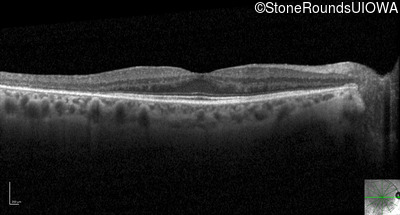

Optical Coherence Tomography - Right - 20/25 -3

Exemplar / OCT Stack

OCT Stack

Optical Coherence Tomography - Left - 20/25 +1